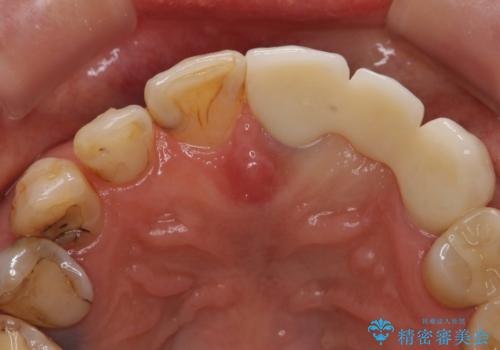

左上2抜歯後、骨および歯肉の回復を待ち、オールセラミッククラウンのブリッジによる欠損補綴を行いました。

- オールセラミッククラウン(sp)…¥130,000×3、仮歯…¥10,000×3、ファイバーコア…¥20,000費用は治療当時の料金となります